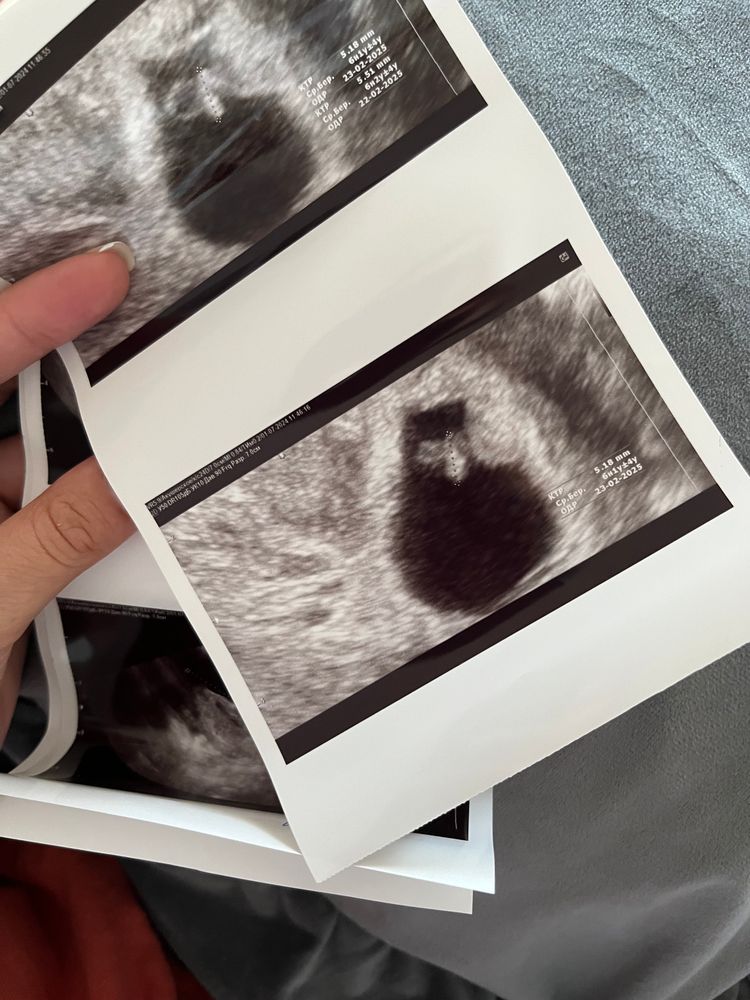

Узи спустя неделю 😊

Узи в 6н6д по месячным,по КТР-5,18 срок 6н2д, человек на месте,сердце стучит 124удара. ЖМ-3,9. Все параметры подросли. Спасибо всем,кто успокоил,что в 5н5д было рано искать эмбрион и СБ,с учетом,что овуляция была позже обычного! Расти крошка ❤️ Шейка 30мм,врач сказала для подстраховки вставлять Утрожестан,будем вставлять 😁